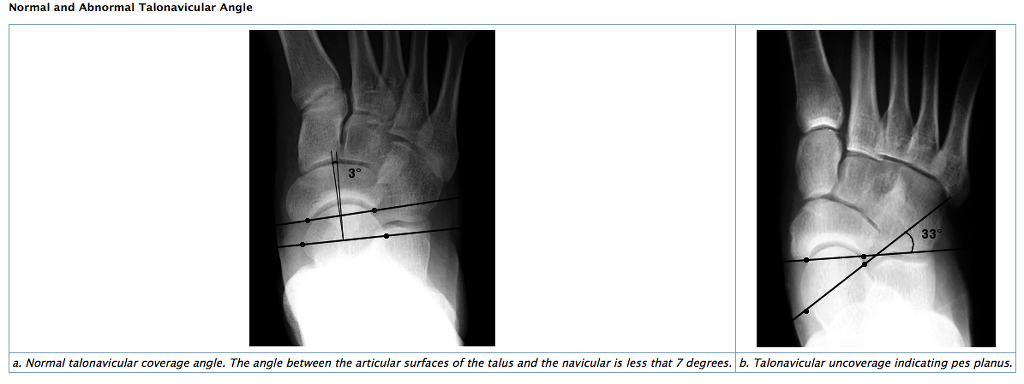

FOREFOOT ABDUCTION

• AP: Talonavicular coverage angle